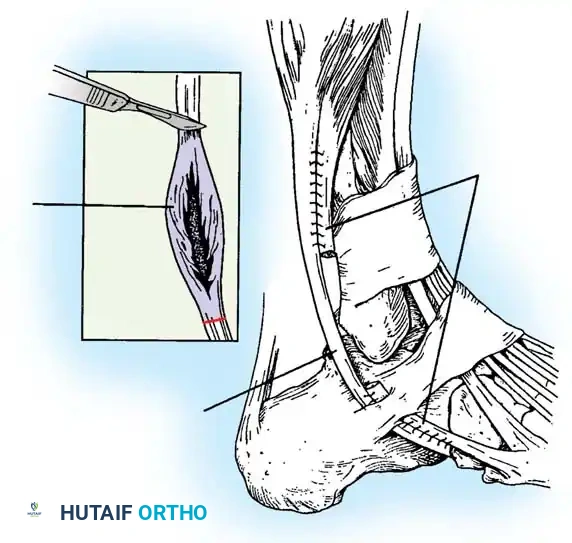

If the tear involves less than 50% of the tendon's cross-sectional area, excise the smaller, degenerative section of the tendon completely. The remaining viable portion is then tubularized to restore a smooth gliding surface. This is achieved using a running 3-0 absorbable, braided suture, burying the knots to minimize friction.

For Grade II Tears (> 50% involvement):

If more than 50% of the peroneus brevis tendon is disrupted and fissured, the remaining section is generally too attenuated to be tubularized effectively. In this scenario, resect the entire diseased segment of the peroneus brevis.

Perform a side-to-side tenodesis of the proximal and distal stumps of the peroneus brevis to the intact peroneus longus tendon.

* The proximal tenodesis should be performed well above the level of the SPR, approximately 3 to 4 cm proximal to the ankle joint, generally at the musculotendinous junction of the peroneus brevis.

* Complete the repair using 2-0 nonabsorbable, braided sutures (e.g., Ethibond or FiberWire), ensuring appropriate tension is maintained to preserve eversion strength.